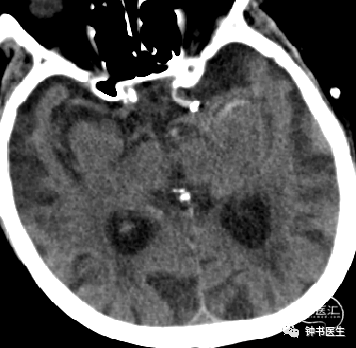

2019-1-10 当地CT

2019-1-12 当地CT

2019-1-12

神经重症治疗思路

血压:90-100mmHg(入院131/66mmHg)

灌注压:60mmHg

脱水:双联

深度镇静镇痛(咪达唑仑+瑞芬)

ICP:15mmHg以内